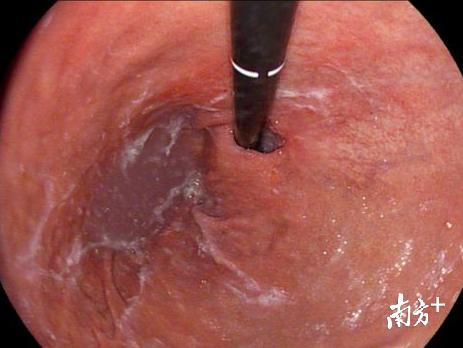

去年9月份,他的妻子看不下去了,拖着他到当地的一家大医院做了检查。检查结果让他非常沮丧——胃镜发现“贲门巨大溃疡”,进一步病理检查诊断为“低分化型、混合型贲门腺癌”,CT检查发现除贲门占位性病变外,“肝胃间隙及腹膜后多发肿大淋巴结”,考虑淋巴结转移,属于进展期的贲门癌。

经过进一步认真细致的检查,CT发现贲门病变侵犯胃壁肌层,累及胃贲门后壁全层,病变周边、小网膜囊、脾胃间隙、肝门部、腹膜后等多发肿大淋巴结。凭借多年胃癌根治术及淋巴结脉络化清扫的经验,同时排除手术禁忌症,多学科讨论认为具备根治手术条件。